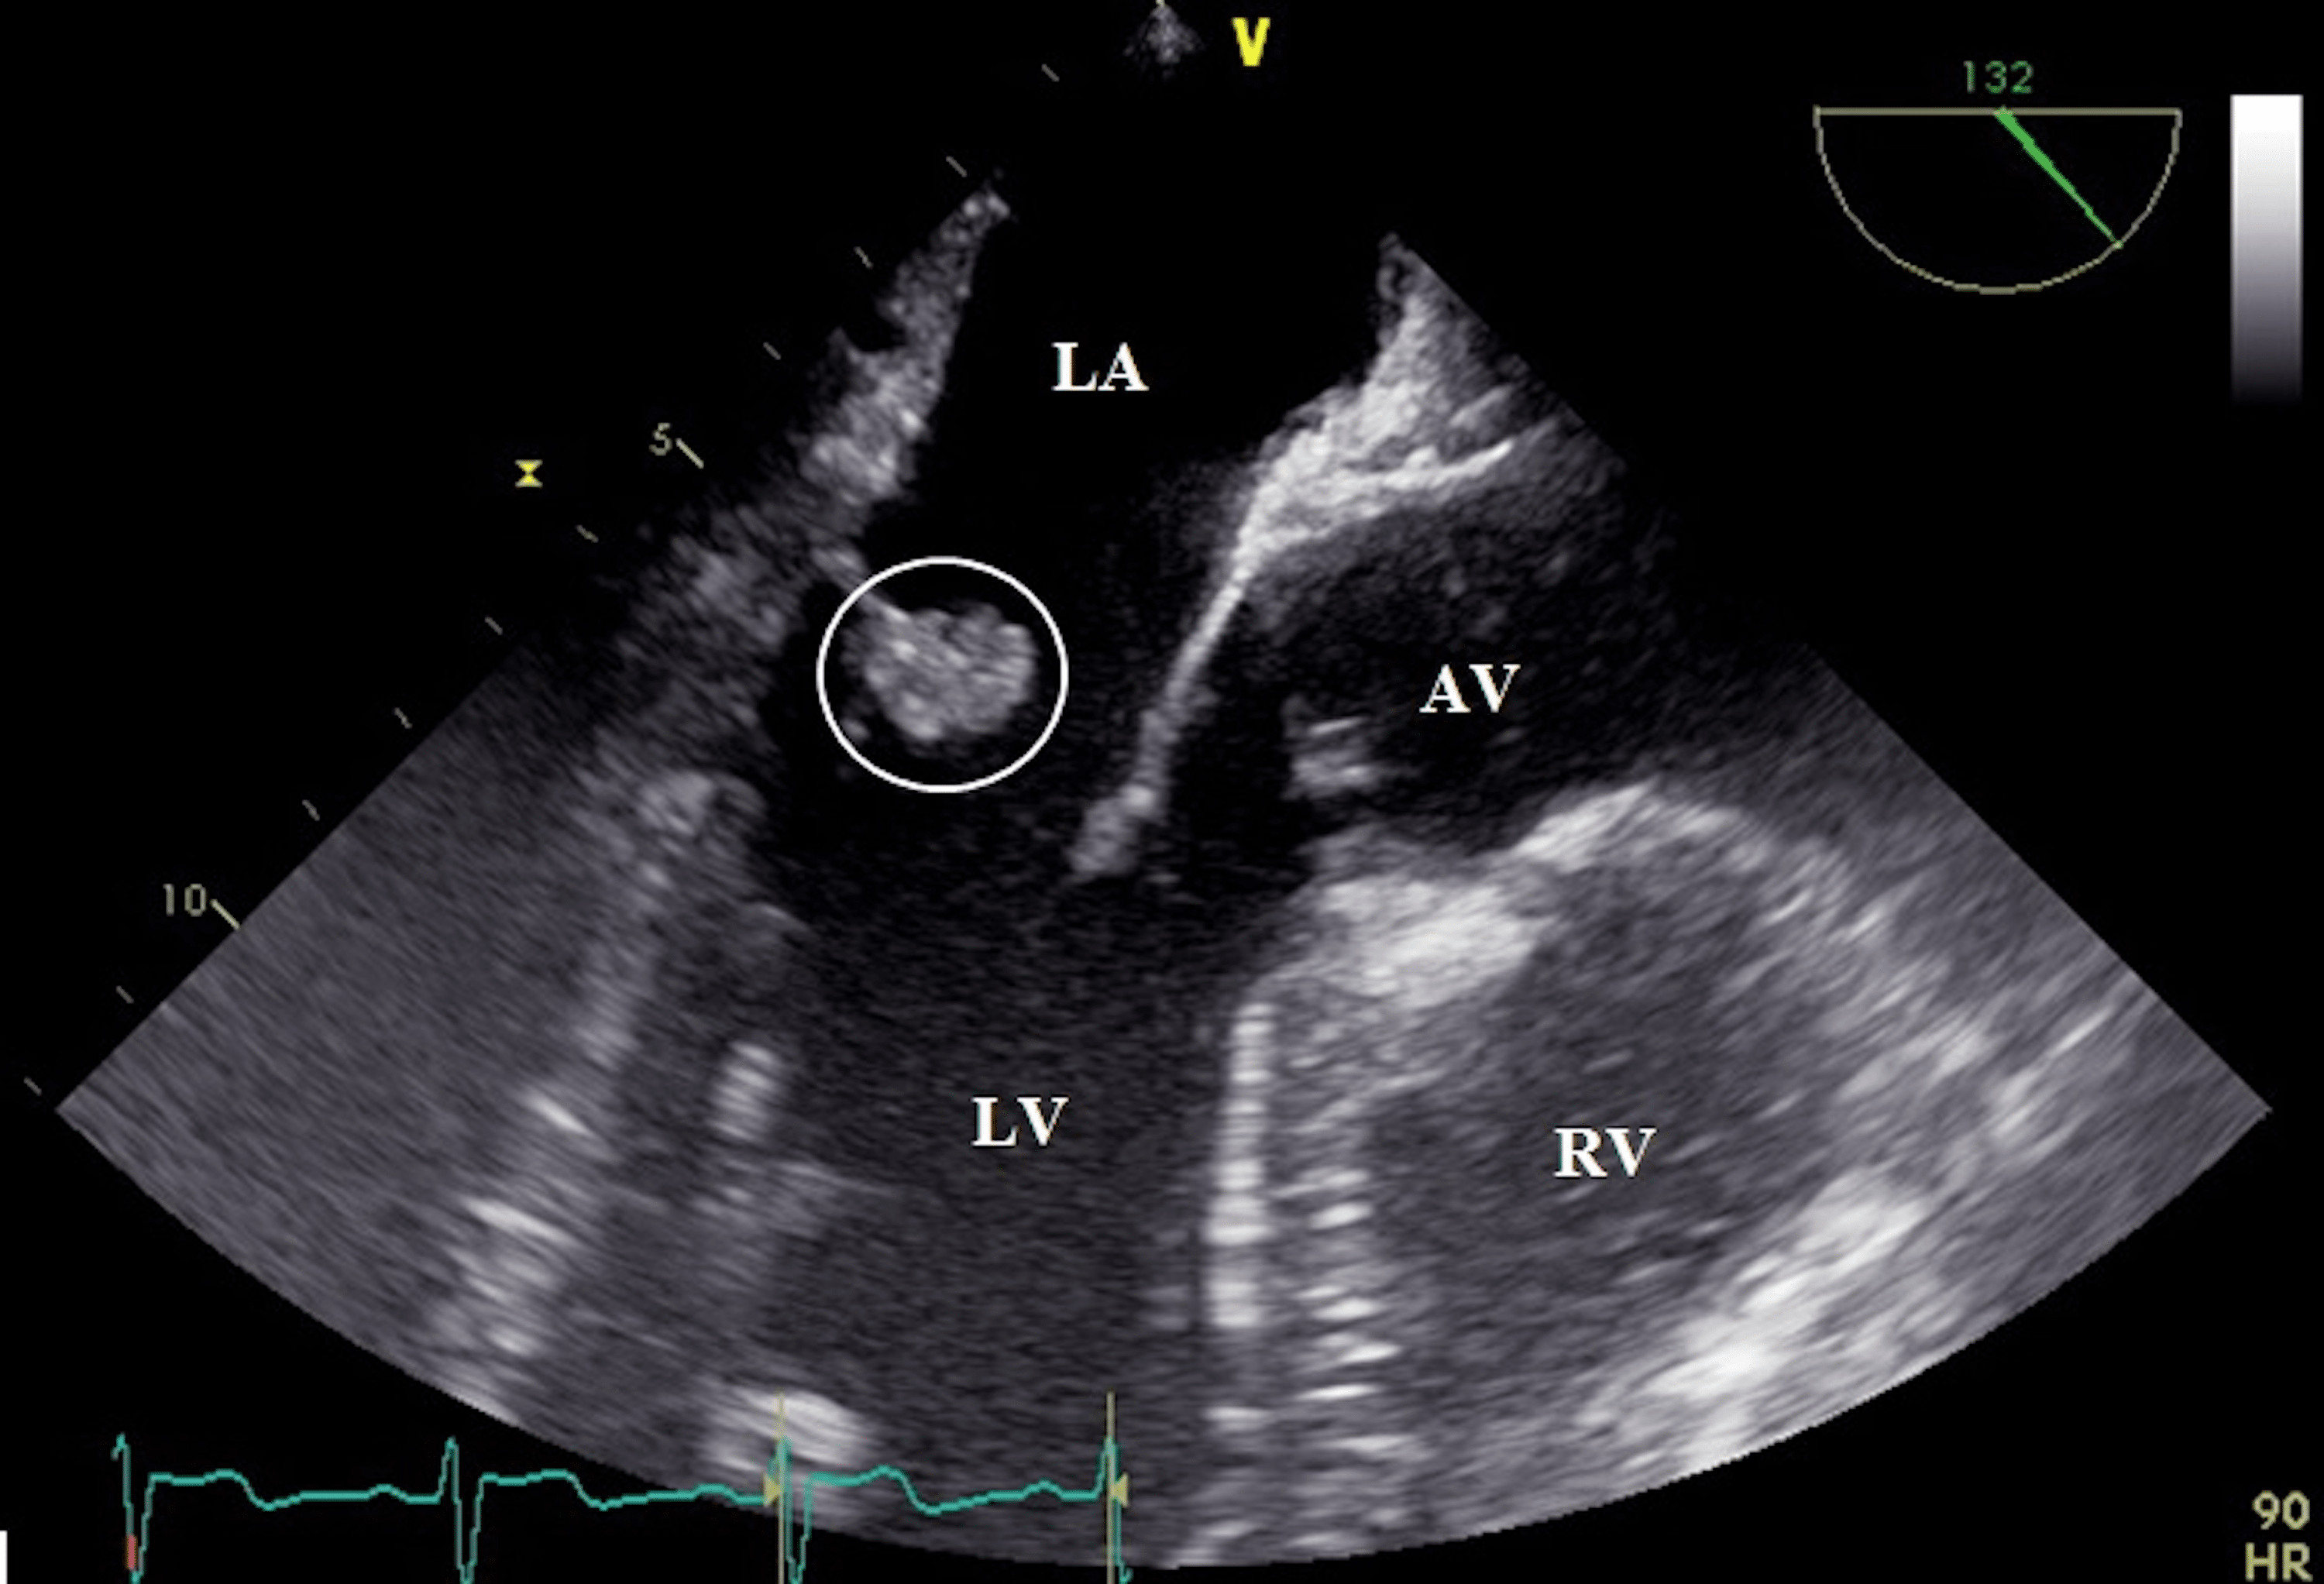

Transthoracic echocardiogram (TTE) showing mobile echodensity (arrow

Mobile Echodensity Definition . A mobile echodensity was noted prolapsing into the la in systole (figure 1a, arrow) which was concerning for a mobile element, thrombus, or. If looking for endocarditis, the mobile echodensity may be a vegetation which is typically accompanied by valvular dysfunction. Patients with cardiac implantable electronic devices (cieds) frequently undergo transthoracic echocardiography (tte). A large mobile echodensity, consistent with vegetation, is attached to the p2 scallop of the mitral valve and prolapses into the. Ice revealed mobile echodensities adherent to the intracardiac leads consistent with either thrombi, vegetation, or. Patients with cardiac implantable electronic devices (cieds) frequently undergo transthoracic echocardiography (tte). Ice revealed mobile echodensities adherent to the intracardiac leads consistent with either thrombi, vegetation, or infected thrombi.